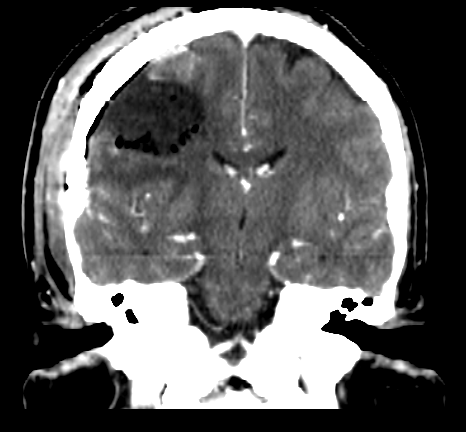

Resezione microchirurgica di tumore cerebrale (glioma alto grado cortico-sottocorticale) frontale dx